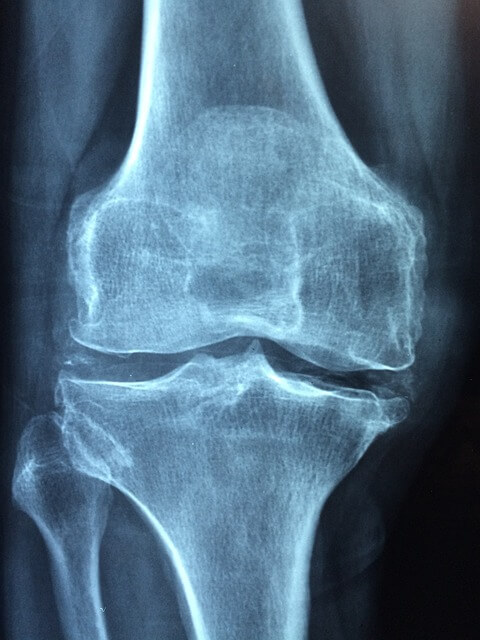

| 약물 요법 뇌 단층촬영(CT)이나 자기공명영상(MRI) 등의 검사를 통해 뇌신경 및 뇌혈관의 상태를 파악한 후, 그에 따른 약물 치료나 수술 치료를 고려합니다. |